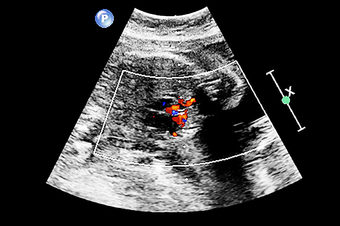

La cardiopatía es la patología congénita de mayor incidencia en España, afectando a 8 de cada 1.000 niños nacidos.